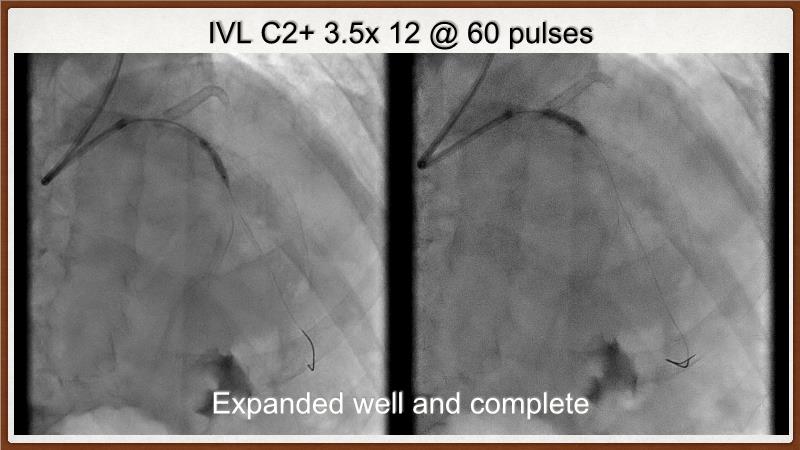

This session explores the challenges of treating calcified lesions during percutaneous coronary intervention (PCI). Learn how calcium can impede stent deliverability and expansion, potentially leading to thrombosis and restenosis. Discover the innovative Shockwave IVL technology, which uses sonic pressure waves to fracture calcium without harming surrounding tissues. The discussion also covers the ongoing challenges of calcified nodules, the importance of intracoronary imaging, and how a layered approach with multiple devices can enhance treatment outcomes. Finally, see how the IVL Shockwave C2+ device facilitates targeted energy delivery for effective PCI.

- To understand the science behind the mechanism of action of intravascular lithotripsy (IVL) for the treatment of calcified lesions

- To uncover practical tips and techniques for IVL in challenging calcified lesions: diffuse, ostial LAD bifurcations and eccentric/calcified nodules